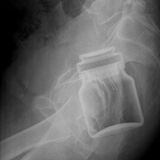

Die Webseite radiopaedia.org zeigt, welche Dinge Ärzte auf Röntgenbildern schon entdeckt haben. Die Aufnahmen wirken skurril und erschreckend zugleich und machen deutlich, wie weit die eingeführten Dinge bereits in den mescnhlichen Darm vordringen können.

Aber Glück im Unglück für die Patienten: Die Gegenstände können meist ohne Operation entfernt werden. Sehen Sie hier einige der spektakulärsten Röntgenaufnahmen. Da runzeln selbst Chirurgen die Stirn.